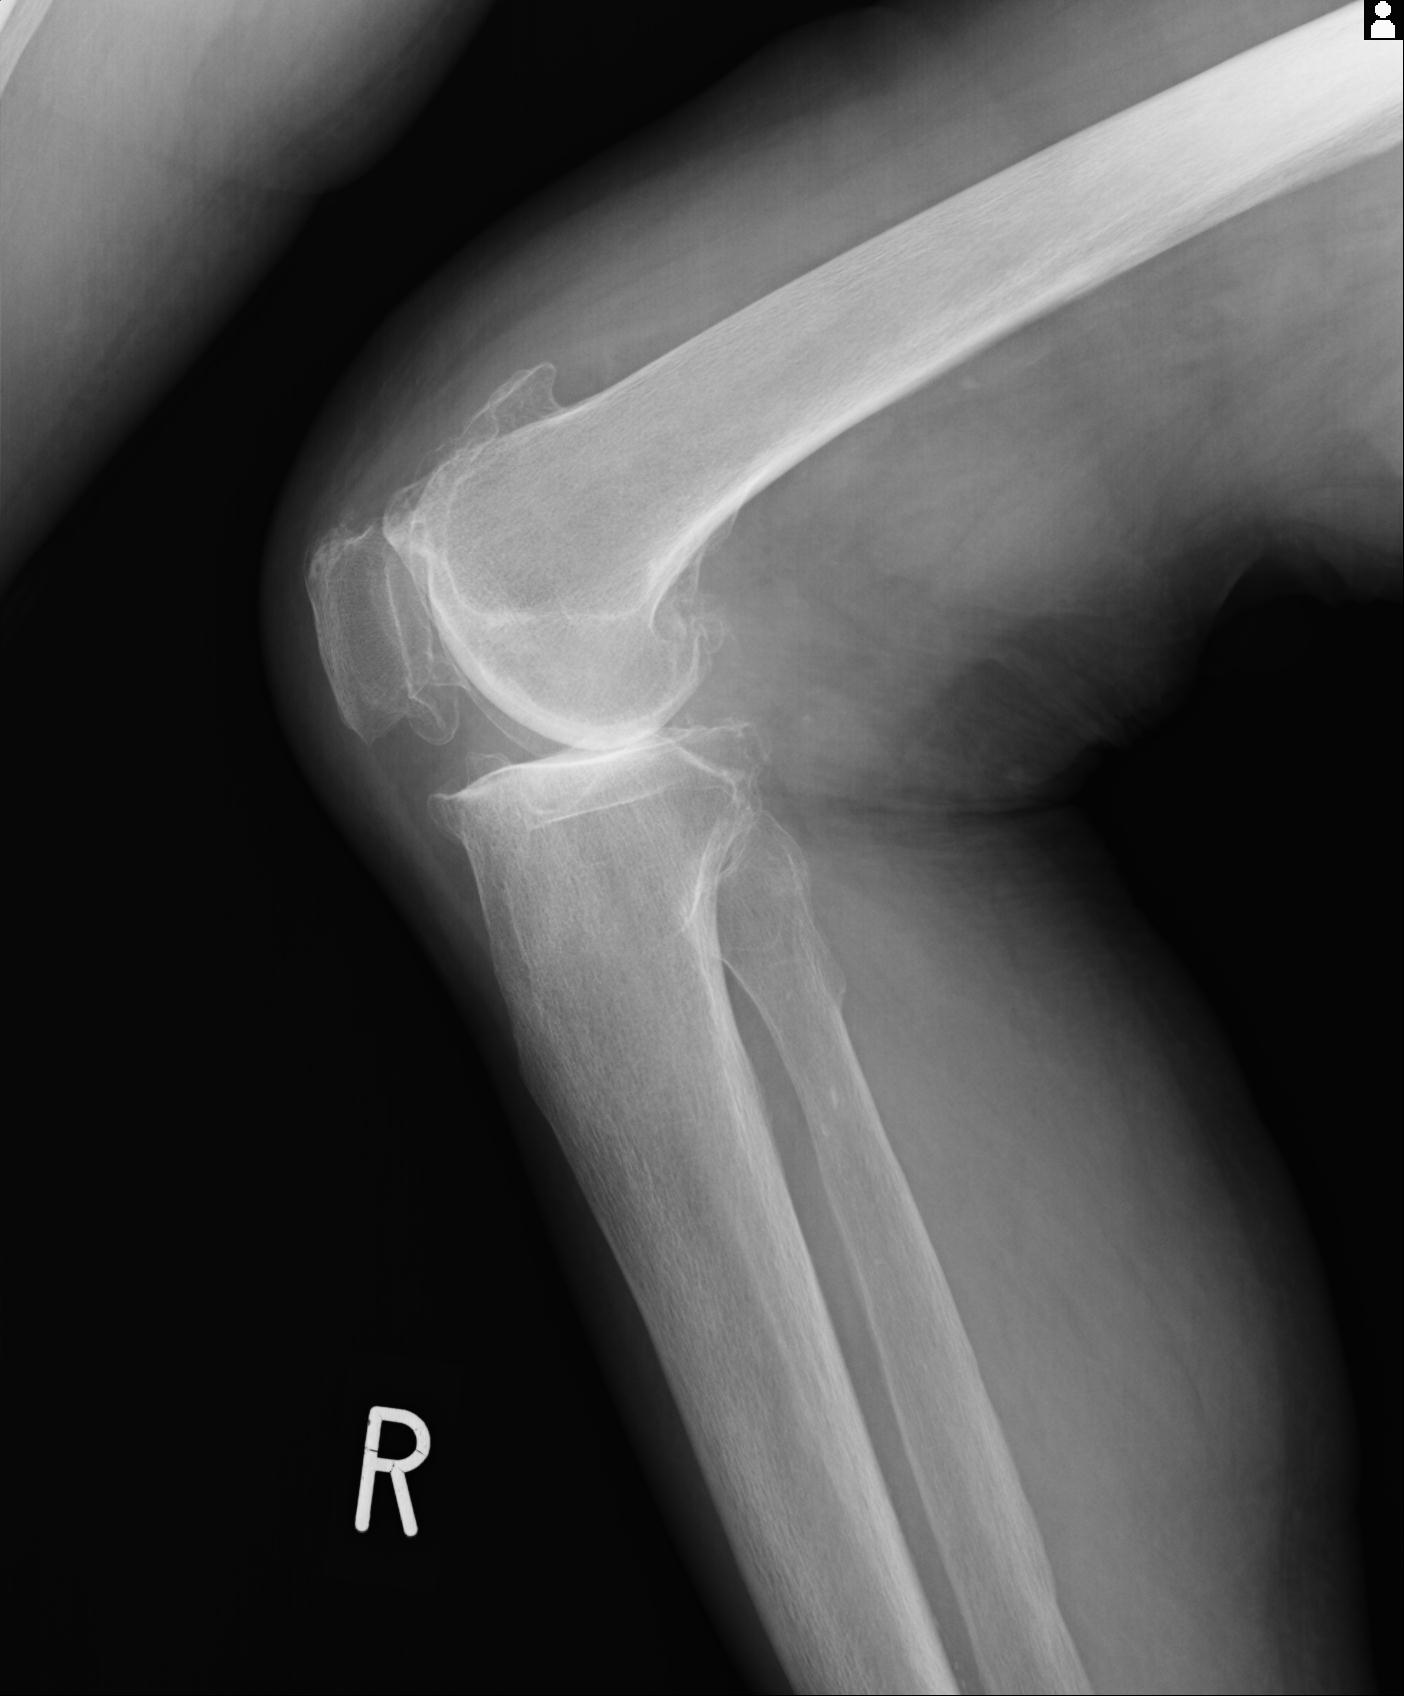

49554 3/13 膝 4R 3/16 4R 1/18 2R 78歳男性 膝蓋骨骨折